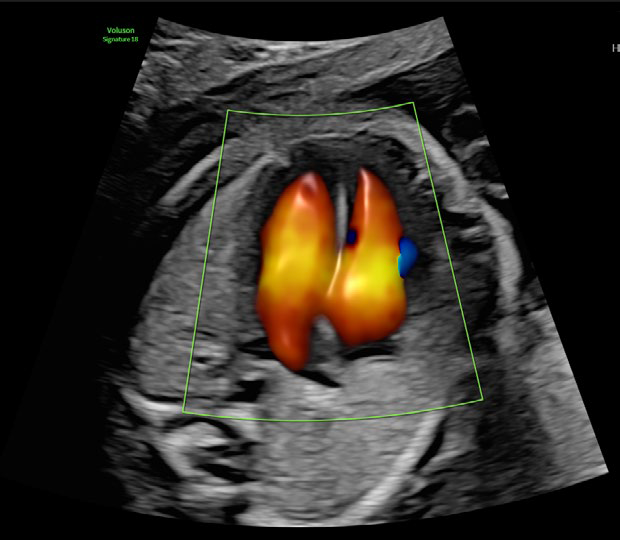

• HDliveTM technologies

Procesamiento rápido de volumen 3D/4D

Calidad de color mejorada y mayor sensibilidad